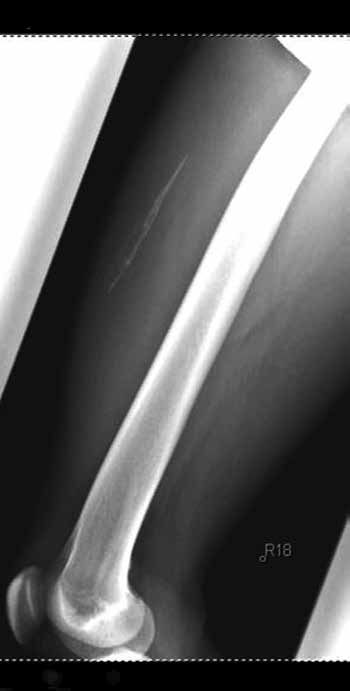

Zu den chronischen Muskelverletzungen zählen auch intramuskuläre Verknöcherungen (Myositis ossificans). Die Verkalkung von Muskelgewebe durch Metaplasie der Histiozyten in Osteoblasten kann posttraumatisch bei ausgeprägter Hämatombildung und Behandlungsfehlern entstehen.

Hierzu zählen etwa frühzeitige Massage des Verletzungsgebietes, ungenügende Ruhigstellung sowie frühzeitiger Trainingsbeginn unter Nichtberücksichtigung der Schmerzen. Führen die Verknöcherungen zu Einschränkungen der Gelenkbeweglichkeit und Schmerzen oder zu starken Beeinträchtigungen der körperlichen Leistungsfähigkeit, können sie operativ entfernt werden (Abb. 2a u. b).

Der Eingriff sollte erst dann erfolgen, wenn die Entzündungsparameter und die alkalische Phosphatase rückläufig sind.